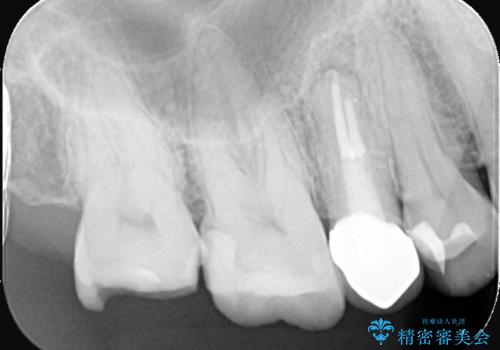

- 何年も前に入れた詰め物が取れたとのことで来院されました。残っている歯の量と強度のことをお話しし、被せものでの治療となりました。

もともとの修復材料とう蝕を除去し、CR裏層の上、オールセラミッククラウンにて修復しました。